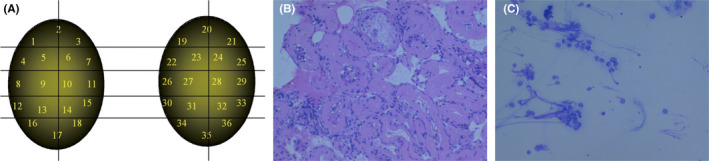

Background: Microdissection TESE has been considered the "gold standard" for retrieving testicular sperm in cases of non-obstructive azoospermia (NOA) despite limited scientific support. Here we compare all aspects of microdissection TESE with testis fine needle aspiration mapping (FNA Mapping) and directed TESE procedures for men with NOA.

Methods: We examine the history of testicular sperm extraction techniques and the rise of advanced technologies with a focus on microdissection TESE and FNA mapping. We summarize the published literature regarding the success rates, complications, and limitations of these two methods.

Main findings: As there are no randomized controlled trials, the best data come from the Cochrane Reviews, which include meta-analyses concluding that the simplest and safest methods of sperm retrieval should be chosen. Although microdissection TESE is popular, recent reports have questioned its value due to the significant hypogonadal consequences. Among alternative procedures, FNA Mapping is a viable and less invasive alternative to microdissection TESE in finding testicular sperm in NOA patients.

Conclusion: Alternatives to microdissection TESE procedures such as FNA Mapping offer several advantages that include similar sperm retrieval success rates, but also less invasiveness and improved understanding of the pathophysiology of NOA.